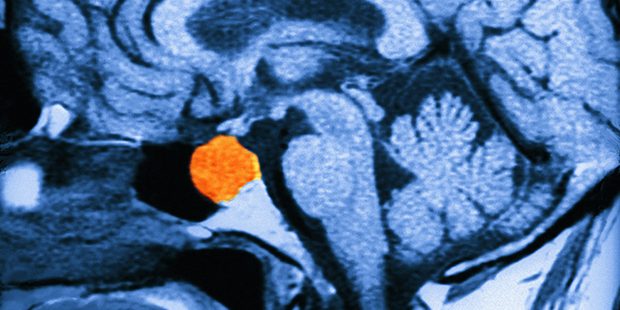

تشخیص هایپرپرولاکتینمی معمولاً با یک آزمایش خون ساده برای سنجش سطح پرولاکتین انجام میشود. در صورتی که سطوح پرولاکتین بالا باشد، پزشک ممکن است از تصویربرداری مغزی مانند MRI برای بررسی غده هیپوفیز استفاده کند تا مشخص شود آیا توموری وجود دارد یا خیر.

۱. تومورهای هیپوفیز (پرولاکتینوما)

- تعریف: پرولاکتینوما یک تومور خوش خیم است که در غده هیپوفیز رشد میکند و سبب تولید بیش از حد پرولاکتین میشود.

- شیوع: این تومورها شایعترین نوع تومورهای ترشحکننده هورمون در هیپوفیز هستند و تقریباً ۴۰% از تومورهای هیپوفیزی را شامل میشوند.

- تأثیرگذاری: حدود ۳۰% تا ۴۰% موارد هایپرپرولاکتینمی به دلیل پرولاکتینوماها است.